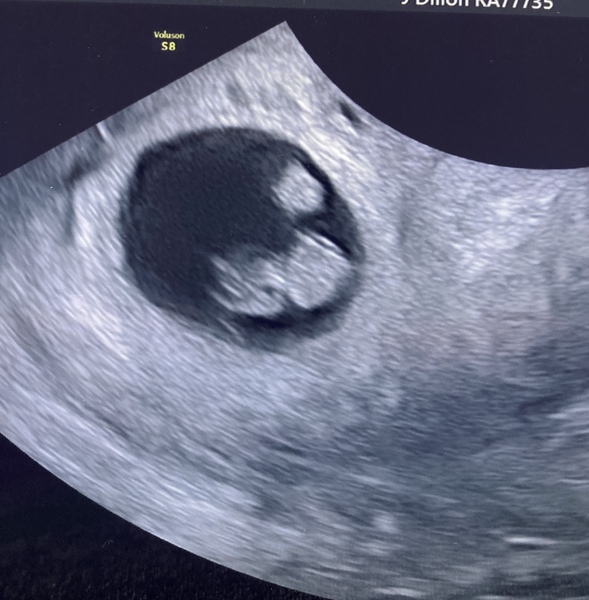

Em39ma · 15/05/2021 11:17

Everything went really well. They think was a twin pregnancy, but only one developed. I’m good with just one.

Now to hope everything stay ok.